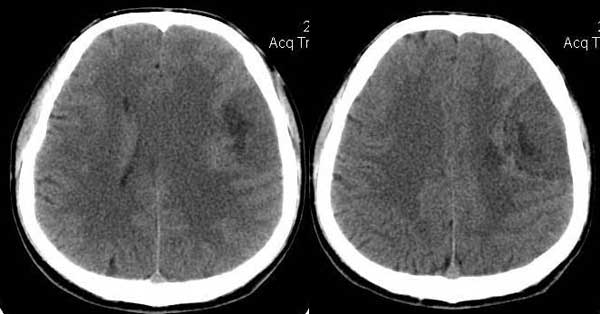

男,35岁。言语不清10余天,口角歪斜。

左颞部稍低密度d形肿块影阴,密度不均,内有不规则囊变区,局部脑白质受压塌陷,肿块周围少许水肿带,中线轻度右移位,增强扫描明显强化,局部颅板有轻微侵蚀,如此大的肿块中线结构移位不明显说明肿块位于脑外,如此强化的脑外肿瘤只有一个------脑膜瘤

平扫呈低密度,与颅内板接触广泛,脑皮层受压内移,增强明显强化,内示不规则的坏死区,周围脑实质内未见明显水肿.

脑膜瘤.